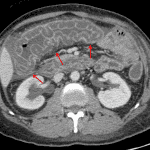

- Multifocal submucosal edema/hyperenhancement from the esophagus through the rectum with most severe involvement of the duodenum and proximal colon

- Urothelial thickening and enhancement of the bilateral ureters, particularly distally

- Diffuse mesenteric edema

Nonspecific multifocal submucosal edema throughout the bowel from the esophagus to the rectum with severe edema of the duodenum and proximal colon. In this patient with lupus, these findings are particularly concerning for a small vessel vasculitis. Infectious/inflammatory enteritis/colitis is also on the differential, but considered less likely given the distribution and discontinuous involvement.

- When the bowel is involved, it is most often the result of small vessel disease (which is not usually directly visualized on imaging) with the SMA distribution being most commonly involved

- Make sure to think about vasculitis and angioedema when you see segmental submucosal edema, particularly when the patient story is not typical for enteritis/colitis or inflammatory bowel disease